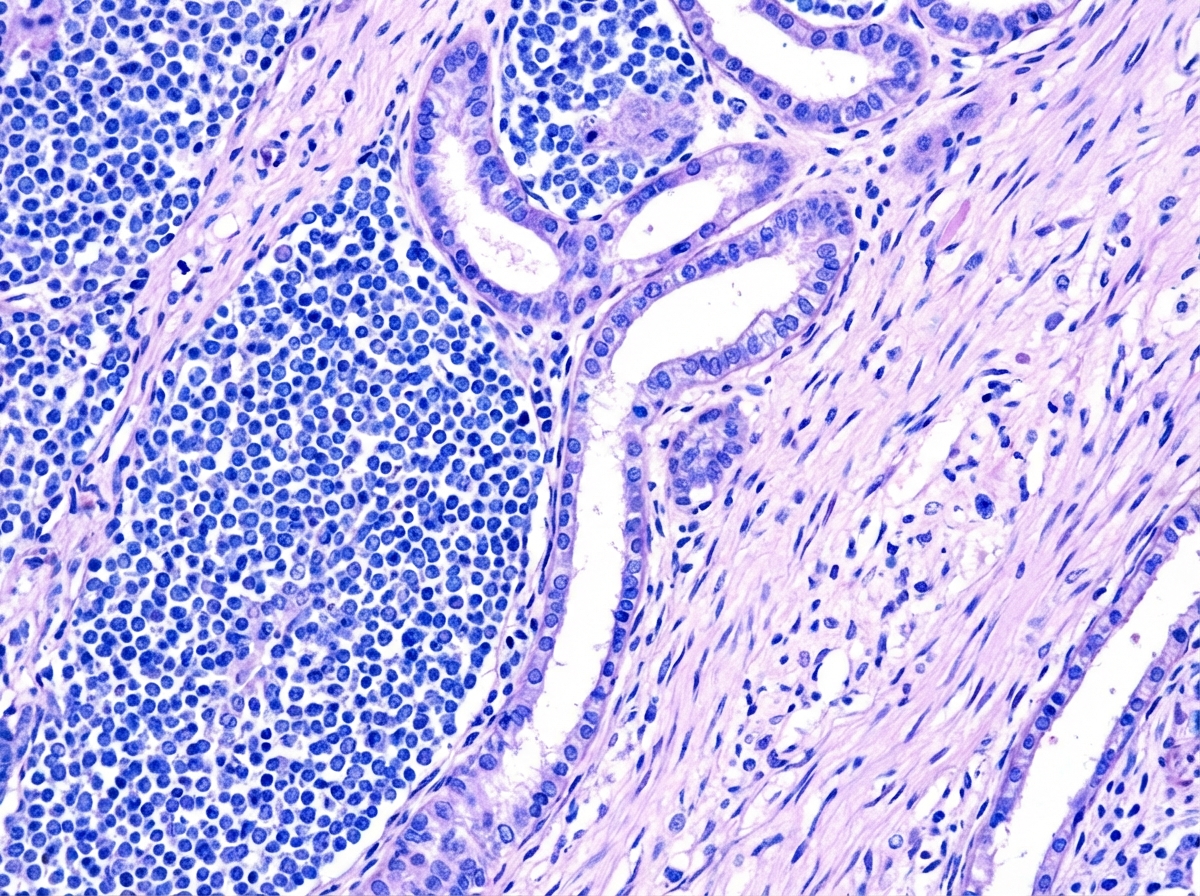

Explanation: **Explanation:** **Wilms' Tumor (Nephroblastoma)** is the most common primary renal malignancy in children, accounting for approximately 95% of all pediatric kidney tumors. It typically presents as an asymptomatic, firm, smooth abdominal mass that does not cross the midline, usually in children aged 2 to 5 years. Pathologically, it is an embryonal tumor derived from the metanephros, characterized by a classic triphasic histology: blastemal, stromal, and epithelial cells. **Analysis of Incorrect Options:** * **Neuroblastoma:** While this is the most common extracranial solid tumor in children, it arises from the adrenal medulla or sympathetic chain, not the kidney parenchyma. Clinically, it presents as an irregular, nodular mass that often crosses the midline. * **Polycystic Kidney Disease (PKD):** This is a genetic disorder characterized by multiple cysts, not a neoplastic tumor. While it causes renal enlargement, it is benign in terms of oncogenesis. * **Renal Cell Carcinoma (RCC):** This is the most common kidney cancer in adults but is extremely rare in young children, typically occurring in adolescents or older populations. **High-Yield Clinical Pearls for NEET-PG:** * **Associated Syndromes:** WAGR syndrome (Wilms, Aniridia, Genitourinary anomalies, Retardation), Denys-Drash syndrome, and Beckwith-Wiedemann syndrome. * **Genetics:** Associated with mutations in the **WT1 gene** (Chromosome 11p13). * **Clinical Caution:** Avoid vigorous palpation of the abdomen in suspected cases to prevent rupture of the tumor capsule and subsequent peritoneal seeding. * **Most Common Site of Metastasis:** The lungs.

Explanation: ***Bleomycin*** - **Bleomycin** is NOT part of standard **Wilms' tumor** chemotherapy protocols (NWTS/COG regimens). - It is primarily used for **germ cell tumors** and **lymphomas**, not for **nephroblastoma**. *Doxorubicin* - **Doxorubicin** is a key component of **intermediate** and **high-risk** Wilms' tumor treatment protocols. - It is used in combination with other agents for **stage III-V** disease or **unfavorable histology**. *Dactinomycin* - **Dactinomycin** is a cornerstone drug in **all risk groups** of Wilms' tumor treatment. - It is part of the **standard two-drug regimen** along with vincristine for **favorable histology** cases. *Vincristine* - **Vincristine** is universally used in **all Wilms' tumor protocols** regardless of stage or histology. - It forms the **backbone** of treatment, often combined with dactinomycin in **low-risk** cases.